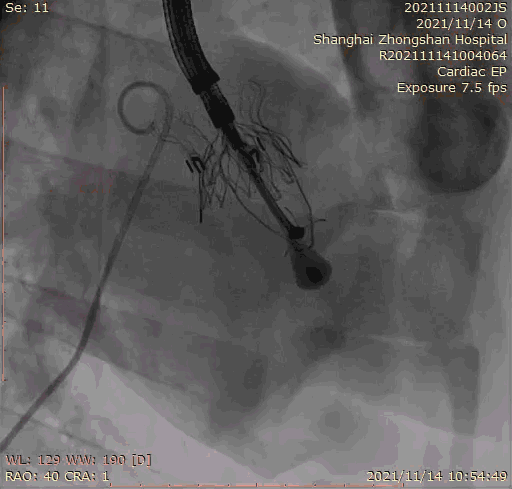

上海中山医院葛均波院士、钱菊英院长、周达新教授、潘文志教授、潘翠珍教授、李伟教授共同完成此次临床前研究。术后葛均波院士对Lux-Valve Plus的器械操作性能给予了高度评价,DSA和超声影像也显示出在本次研究中Lux-Valve Plus的安全性和有效性俱佳。

本次临床前研究经右侧颈静脉置入LuX-Valve Plus输送系统可调弯鞘管,在DSA及超声引导下将人工三尖瓣瓣膜植入到原有三尖瓣位置,利用独特的锚定技术将人工瓣膜支架可靠固定在预定的位置。

Lux-Valve是全球第一款具有我国完全自主知识产权的经导管介入三尖瓣置换系统,利用前瓣夹持及室间隔锚定的复合方式进行瓣膜装置的固定,不依赖瓣环径向支撑力,同时采用自适应复合裙边材料,有效的贴合密封柔软的三尖瓣瓣环,针对于三尖瓣返流的患者有优异的疗效。Lux-Valve Plus采用全新的经血管输送系统,经颈静脉入路创伤更小,可以进一步降低手术风险。相信在后期正式临床研究开展中,Lux-Valve Plus必定会为更多的三尖瓣反流患者带来福音。